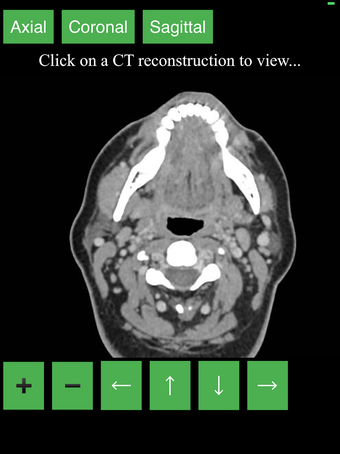

Ta aplikacja jest najwygodniejszym sposobem na przeglądanie i badanie przekrojowo anatomii człowieka na skanie CT. Może być używana jako materiał referencyjny i narzędzie edukacyjne.

Aplikacja wyświetla przekrojowy obraz tomograficzny ciała człowieka i używa systemu kodowania kolorów, aby łatwo identyfikować różne struktury tkanek miękkich i kości. Może również być używana do badania określonej części ciała, takiej jak szyja, czaszka, obręcz barkowa lub klatka piersiowa.

Użytkownik może przesuwać obraz i powiększać go, aby lepiej zidentyfikować struktury i powiększyć obraz do dalszych badań.